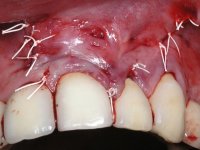

I have decided to replace the old fixed partial dentures to improve aesthetics and simultaneously eliminate root exposures. In order to do so, periodontal plastic surgery – tunneling procedure - was a priority, to increase the thickness of the soft-tissue and to do a coronal repositioning to reduce the root exposures.

PERIODONTAL PLASTIC SURGERY:

Dr. Manuel Neves, Clínica Dr. Manuel Neves.